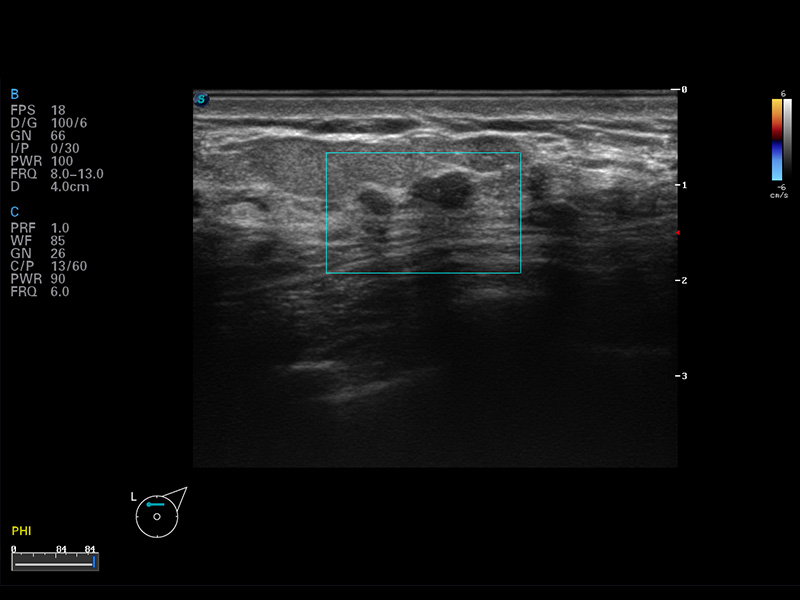

S8 EXP便携式彩色多普勒超声诊断仪是银河优越会研发的高端全身应用型便携彩超。高通道的VIS平台融合可视化(Visual)、智能化(Intelligent)和人性化(Smart)的特点,配以银河优越会自主研发生产的探头大家族,使您能够快速、准确的获得病人信息,提高工作效率的同时减轻疲劳。

成像技术

μ-Scan微米成像

谐波成像

空间复合成像